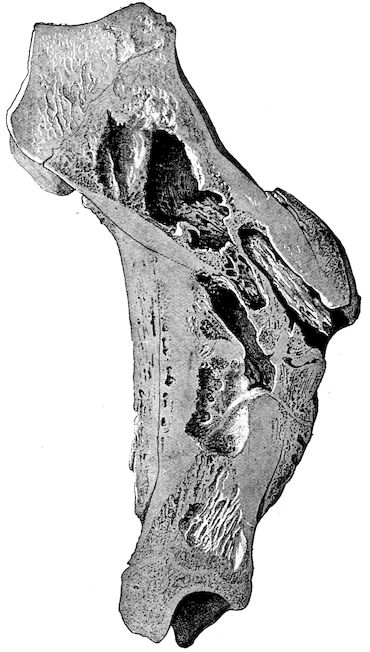

Fig. 1.—Rachitis in a young goat.

Fig. 1.—Rachitis in a young goat.